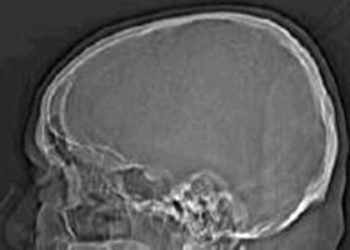

#VisualAbstract Adjunctive Middle Meningeal#VisualAbstract Artery Embolization for Subacute and Chronic Subdural Hematomas

1. In this randomized controlled trial, middle meningeal artery embolization plus surgical evacuation was associated with a lower risk of hematoma ...